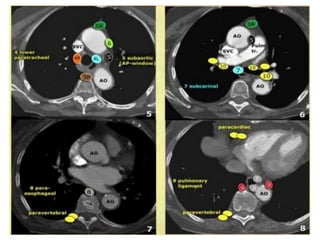

HẠCH TRUNG THẤT

PHAÂN LOAÏI HAÏCH THEO VUØNG

American Thoracic Society

NHOÙM HAÏCH TRUNG THAÁT TREÂN (1-4)

• 1. Trung thaát cao nhaát: treân tónh maïch thaân tay ñaàu

(T).

• 2. Caïnh khí quaûn treân: treân cung ñoäng maïch chuû

nhöng döôùi tónh maïch thaân tay ñaàu (T).

• 3. Tröôùc maïch maùu hay tröôùc coät soáng.

• 4. Caïnh khí quaûn döôùi.

NHOÙM HAÏCH CHUÛ (5-6)

• 5. Döôùi ñoäng maïch chuû.

• 6. Caïnh ñoäng maïch chuû: naèm tröôùc ngoaøi ñoäng

maïch chuû leân vaø cung ñoäng maïch chuû.

NHOÙM HAÏCH TRUNG THAÁT DÖÔÙI (7-9)

• 7. Döôùi carina

• 8. Caïnh thöïc quaûn (döôùi carina).

• 9. Daây chaèng phoåi.

NHOÙM HAÏCH NAÈM ÔÛ ROÁN, GIAN THUØY,

THUØY, PHAÂN THUØY, HAÏ PHAÂN THUØY

(10-14)

1. TRUNG THAÁT CAO NHAÁT

Tónh maïch thaân tay ñaàu vaãn coøn naèm beân (T) ñöôøng giöõa.

Haïch naèm treân ñöôøng maø tónh maïch thaân tay ñaàu (T)

chaïy ngang qua tröôùc khí quaûn

2.CAÏNH KHÍ QUAÛN TREÂN

Coù haïch nhoû tröôùc maïch maùu -3A

3. HAÏCH TRÖÔÙC MAÏCH MAÙU VAØ TRÖÔÙC SOÁNG

Khoâng naèm caïnh khí quaûn- naèm tröôùc maïch maùu (3A) hay sau thöïc quaûn tröôùc coät soáng (3P)

Haïch tröôùc maïch maùu -3A.

Haïch caïnh khí quaûn döôùi -4R.

4. HAÏCH CAÏNH KHÍ QUAÛN DÖÔÙI

Naèm döôùi ñöôøng ngang veõ tieáp tuyeán bôø treân

cung ñoäng maïch chuû.

4R-Haïch naèm beân (P) ñöôøng giöõa khí quaûn.

4L-Haïch naèm beân (T) ñöôøng giöõa khí quaûn môû roäng ñeán pheá quaûn

chính (T) ôû möùc bôø treân cuûa pheá quaûn thuøy treân (T)-Bao goàm nhoùm

haïch caïnh khí quaûn naèm ôû möùc trung gian ñeán daây chaèng ñoäng maïch.

5. HAÏCH DÖÔÙI ÑOÄNG MAÏCH CHUÛ: ngoaøi daây chaèng ñoäng maïch.

6. HAÏCH CAÏNH ÑOÄNG MAÏCH CHUÛ

Naèm tröôùc ngoaøi ñoäng maïch chuû leân, cung ñoäng maïch chuû, döôùi bôø treân cung

ñoäng maïch chuû.

7.NHOÙM HAÏCH DÖÔÙI CARINA

8 NHOÙM HAÏCH CAÏNH THÖÏC QUAÛN

Naèm döôùi carina.

Caïnh thaønh thöïc quaûn, beân (P) hay (T) ñöôøng giöõa.

9. NHOÙM HAÏCH DAÂY CHAÈNG PHOÅI

Naèm beân trong daây chaèng phoåi, bao goàm haïch naèm ôû thaønh sau vaø

phaàn thaáp cuûa tónh maïch phoåi döôùi.

10. NHOÙM HAÏCH ROÁN PHOÅI